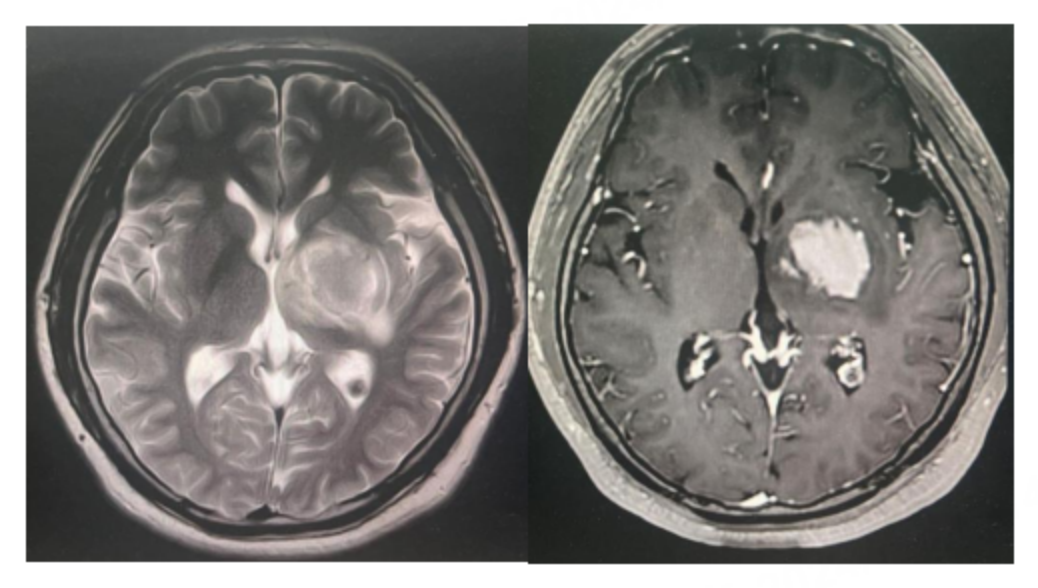

原发性中枢神经系统淋巴瘤(PCNSL)是一种罕见的结外非霍奇金淋巴瘤(NHL),病灶范围局限于脑实质、脊髓、软脑膜和眼,其中95%以上的患者病理类型为弥漫性大B细胞淋巴瘤(DLBCL)。

本文通过一例局限期小细胞肺癌脑转移瘤患者的治疗过程,探讨了替尼泊苷联合化疗方案在提高治疗效果方面的潜力。